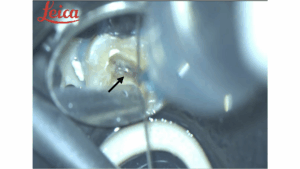

治療を始める前に、青いゴムのシート(ラバーダム)で歯(矢印)

を囲み、さらに隙間を水色のレジンで埋めて密閉します。これにより、唾液に含まれる細菌が歯の中に侵入するのを防ぎ、無菌に近い状態で治療を進めることができます。

次に、歯科用顕微鏡(マイクロスコープ)で歯の内部を大きく映し出します。この段階の視野でも、歯の神経からの微かな出血が認められます(矢印部)。これが、処置すべき場所を見つける最初の目印となります。